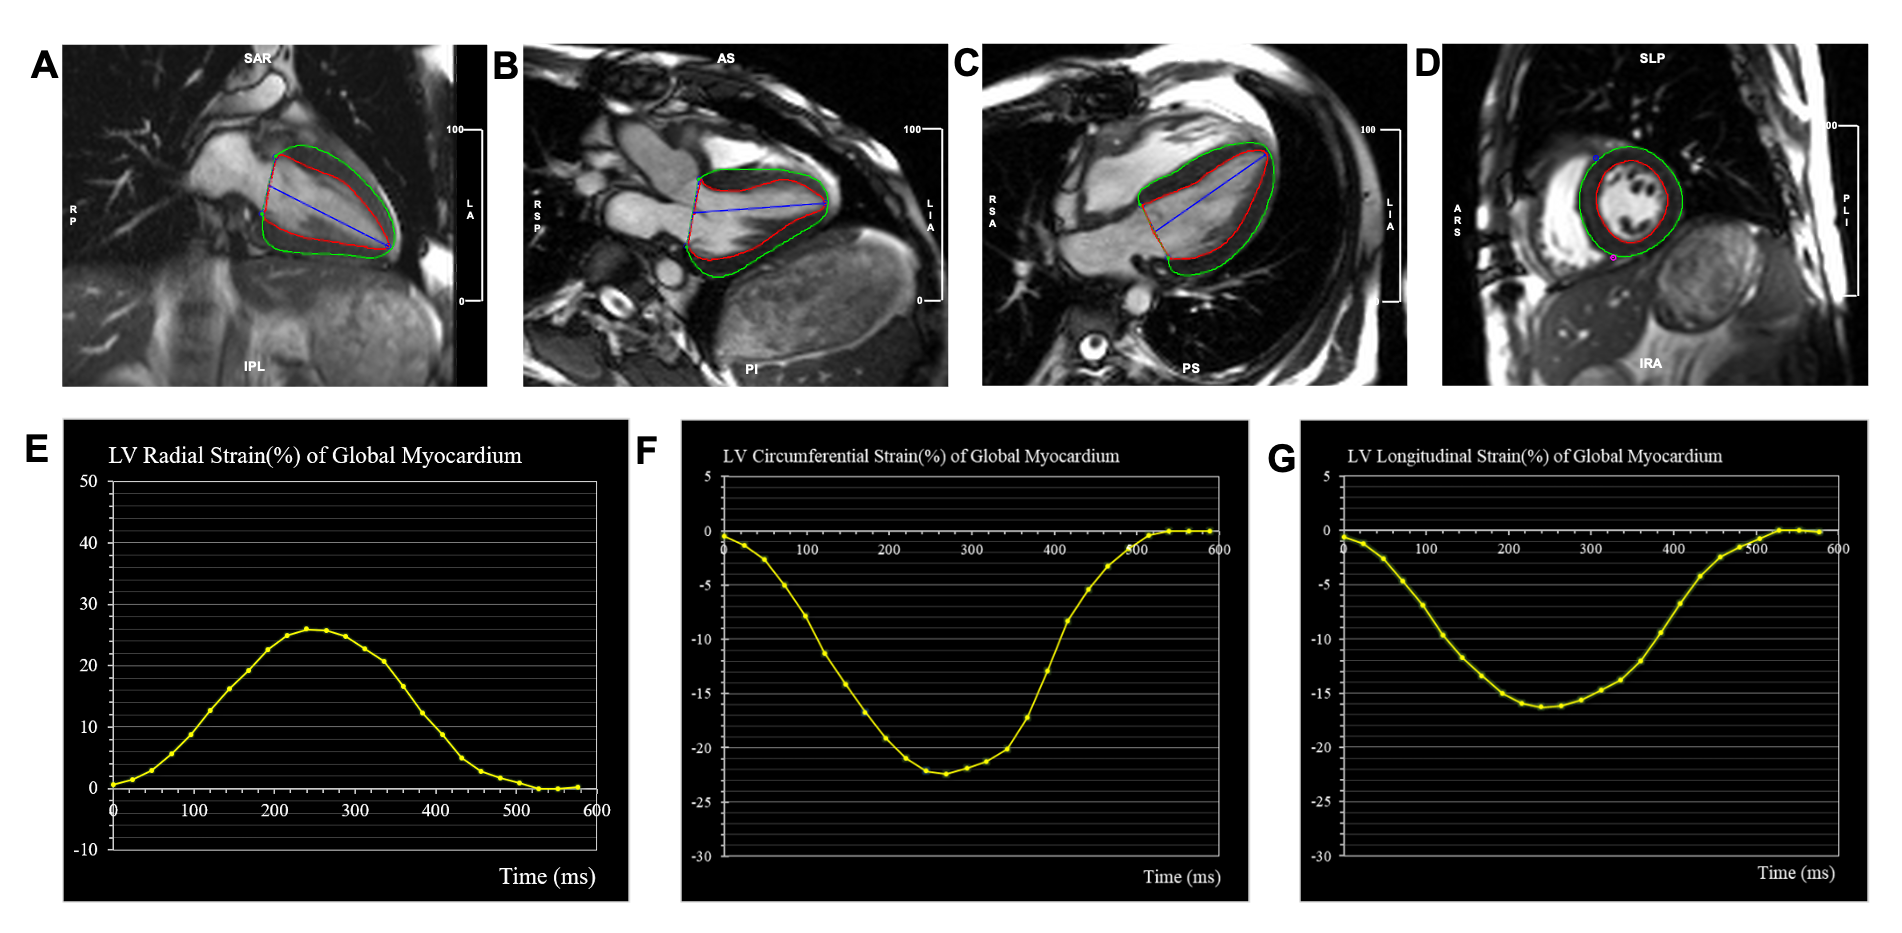

Sixty-one patients who underwent CMR within 24 hours before or after a routine endomyocardial biopsy were included in this study. CMR images were taken with 1.5-T & 3.0T scanners (Magnetom Avanto, Siemens, Germany; Ingenia CX, Philips Healthcare, the Netherlands) equipped with an 8-channel cardiac coil. Cine images included a stack of parallel short-axis and three long-axis views (2-, 3-, and 4-chamber) with a balanced steady-state free-precession. All strain parameters were obtained using a commercial software cvi42 (Circle Cardiovascular Imaging Inc., Calgary, Alberta, Canada) by experienced radiologist with more than 5 years of training in cardiac imaging. Cine images were imported into the tissue tracking module of the cvi42. The endocardial and epicardial borders of the LV wall were demarcated semi-automatically on end-diastolic images (Figure 1). ACAR was categorized according to the International Society for Heart and Lung Transplantation (ISHLT) grade. CMR-FT parameters were compared using the endomyocardial biopsy findings. Univariable logistic regression was performed, and variables with P values < 0.10 in the univariable analysis included in subsequent multivariable logistic regression to predict the best diagnostic factors. Receiver operating characteristic (ROC) curve analysis was used to evaluate the ability of different strain parameters to detect rejection.

Figure 1: Representative images of cardiovascular magnetic resonance feature tracking (CMR-FT) strain. Measurement of left ventricular (LV) strain by CMR-FT (A-D). LV endocardial (red line) and epicardial (green line) borders were detected automatically with manual correction at LV end-diastole in 2-chamber (A), 3-chamber (B), 4-chamber (C), and short axis (D) views, respectively. Global radial (E) circumferential (F) longitudinal (G) strain curves.